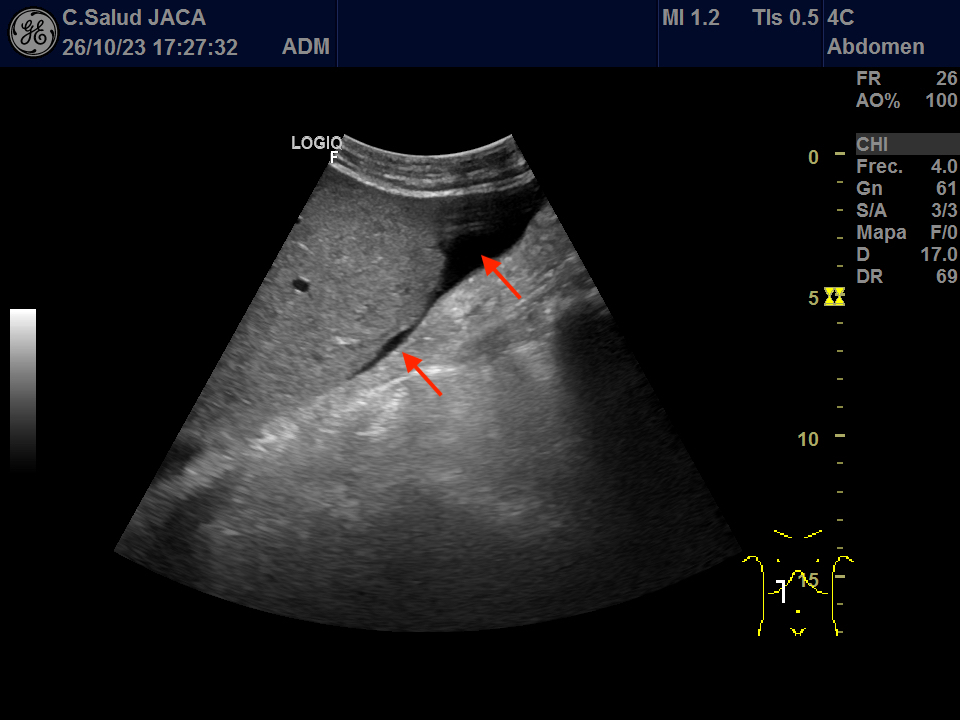

Presentamos las ilustrativas imágenes ecográficas obtenidas con sonda convex en la consulta de su Médico de Familia, que muestran derrame pleural y pericárdico, gran dilatación de ambas aurículas (ventana subxifoidea), ascitis, engrosamiento de 30 mm de la cava a su entrada en la aurícula derecha, que no se modifica con la inspiración, y congestión igualmente de las venas suprahepáticas.